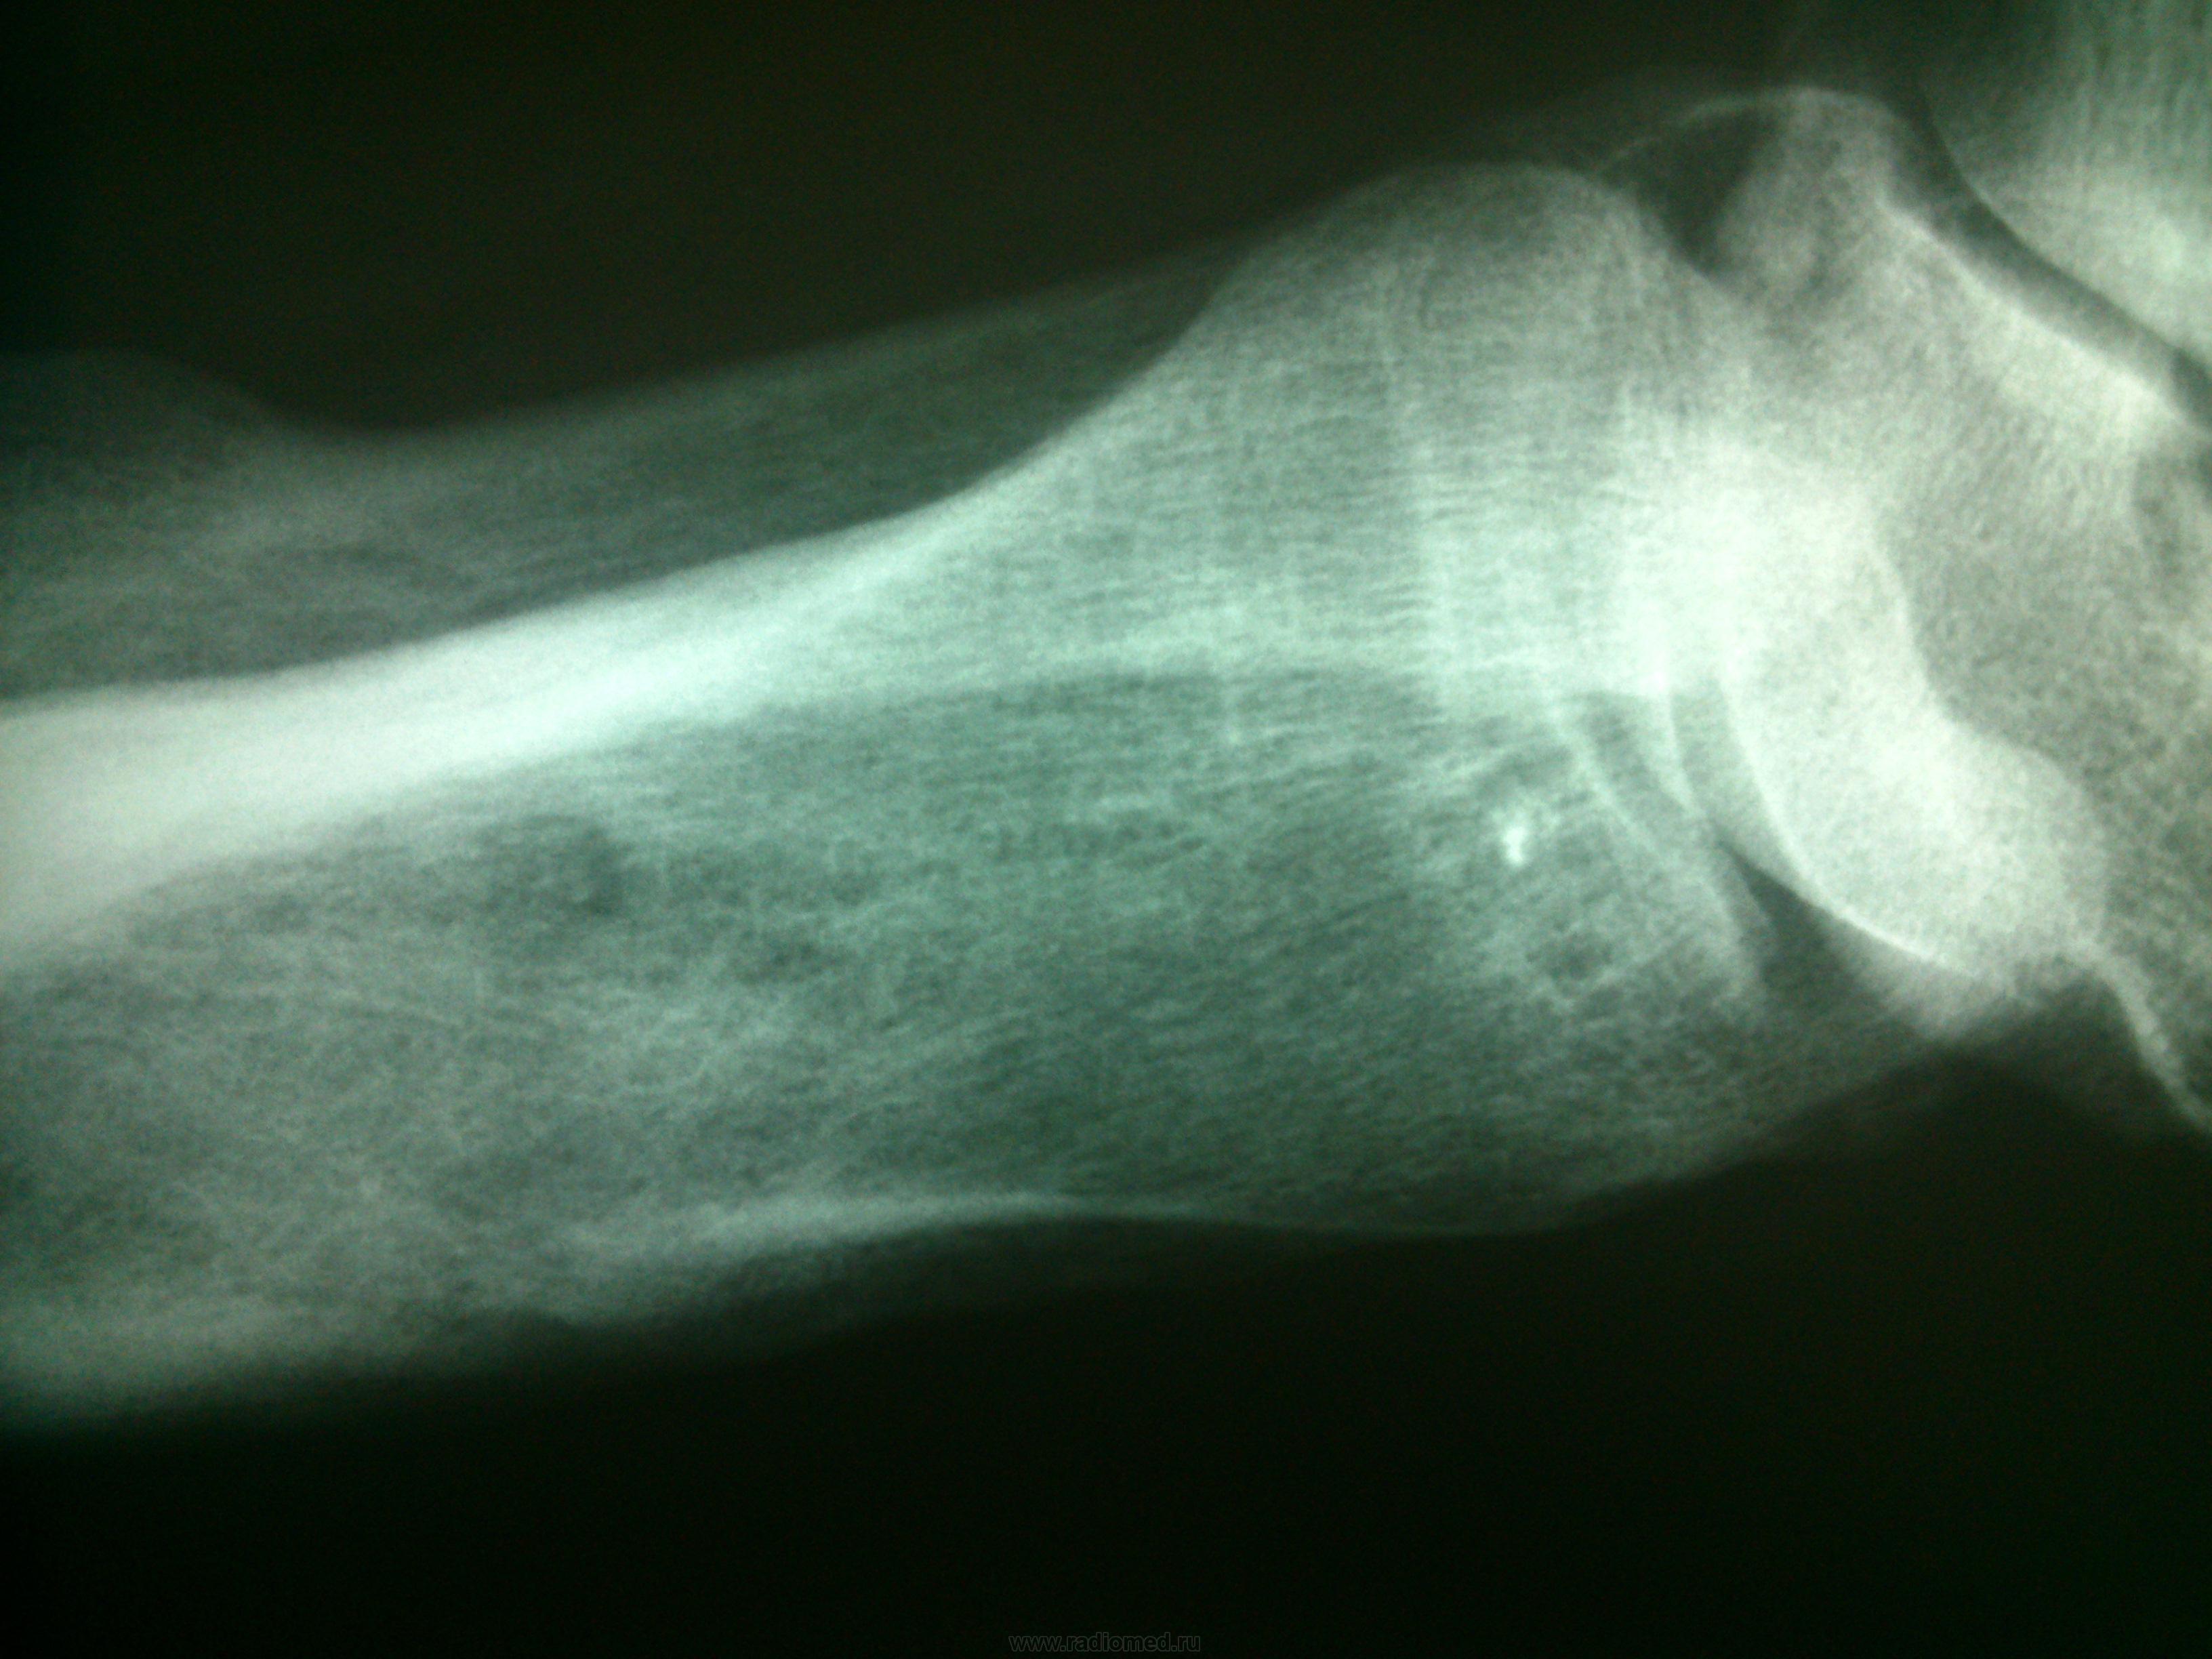

Много оскольчатый, открытый перелом со смещением отломков нижней трети обеих берцовых костей, с дальнейшей репозицией и наложением металлоконструкции! Мне кажется, что тут имеет место быть отсроченный остеомиелит(?), хотя внешних изменений мягких тканей над переломом не наблюдается ( покраснение кожи и повышение локальной температуры).Помогите(((Может на КТ отправить!

Остеомиелита без клиники не бывает. Мало того, при наличии клиники рентгеновские признаки остеомиелита возникают в среднем на 21 день болезни (обратное развитие также отстает). Поэтому - посттравматическоая деформация и изменение структуры н/3 левой большеберцовой кости.

В малоберцовой до сих пор "остаточная линия перелома" виднеется